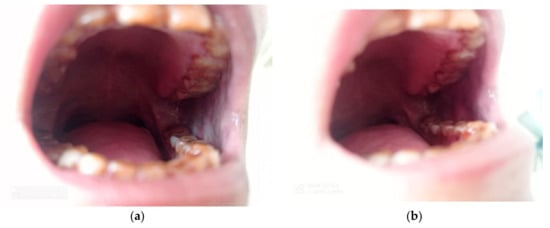

Figure 17. Tobacco Chewer’s Keratosis Prior (a) and After (b) the use of Curcumin.

Healthcare 10 01507 g017

Figure 18. Hyperkeratotic Lesion on Left Buccal Mucosa Prior (a) and After (b) Intervention with Curcumin.

Healthcare 10 01507 g018

After 2 months of intervention with curcumin gel in the Study group, two swabs were again taken for cytomorphometric analysis and candida colonization and speciation as mentioned above. The same procedure as mentioned above for comparison and evaluation to obtain values for cytomorphometric analysis and candida colonization and speciation before and after the use of curcumin was followed (Figure 17 and Figure 18).